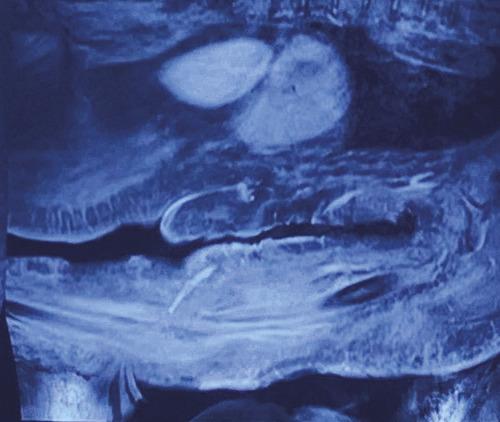

Après quelques jours de traitement immunosuppresseur, une douleur intense et insomniante s’installe, avec érythème et tuméfaction du membre supérieur gauche. Les examens complémentaires retrouvent une protéine C-réactive (CRP) à 300 mg/L, des hémocultures stériles, une échographie Doppler artérioveineuse sans thrombose. Le diagnostic d’une dermohypodermite bactérienne non nécrosante est évoqué dans un premier temps. La patiente est alors traitée par antibiothérapie (amoxicilline et acide clavulanique). L’évolution est défavorable, avec apparition de lésions nécrotico-hémorragiques rapidement extensives (fig. 2 ). Une imagerie par résonance magnétique (IRM) [fig. 3 ] montre une infiltration des parties molles sous-cutanées, des loges musculaires associées à des bulles d’air, en faveur d’une fasciite nécrosante. Une exploration chirurgicale permet de réaliser des biopsies profondes au niveau du fascia et du muscle. Le résultat histologique, après coloration de Grocott, montre une cryptococcose avec multiples foyers de nécrose de liquéfaction (fig. 4 ). Le diagnostic de fasciite nécrosante cryptococcique est finalement retenu. La recherche de l’antigène sérique cryptococique est positive (1 : 2 000, test d’agglutination au latex). La sérologie VIH (virus de l’immunodéficience humaine) est négative. À défaut d’amphotéricine B, du fluconazole à la dose de 400 mg/j est administré. L’évolution a été défavorable, avec décès à la suite d’un choc septique.